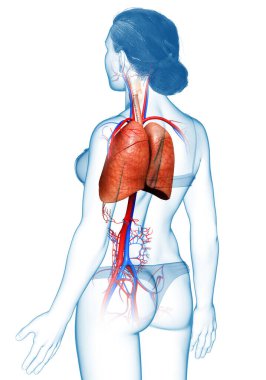

çizim, pulmoner dolaşım

ArkaplankişiİnsanKadınkanİlaçSolunumAvrupa DiliKardiyolojikalpdüzresim çalışmasıAkciğerSistemkemergemiüstünvenanatomiNormalauricletedavülarterAzalanyükselenCavaaortvena cavatorasikaşağıPulmonerventrikül20 30 yıldüz arka planKan damarıSolunum SistemiKan dolaşımıPnömolojiaortik kemerinen aortPulmoner dolaşımtorasik aortyükselen aortaPulmoner arterBenzer İçerikler